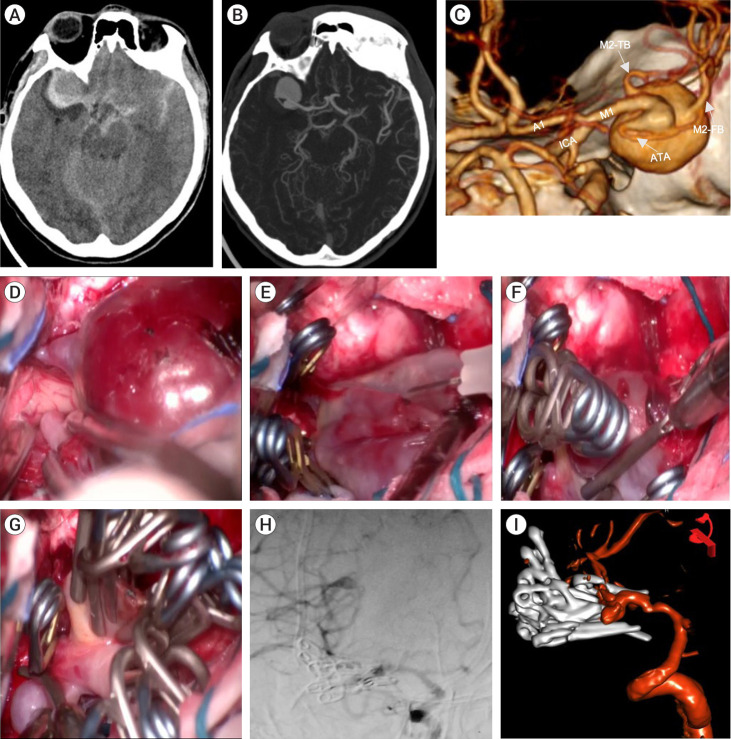

复杂动脉瘤是当代神经外科的治疗难题。目前已提出了几种显微外科和血管内治疗技术。栅栏式剪切技术使用栅栏式夹子,这种夹子的堆叠不是为了重建动脉瘤的颈部,而是通过重建穹顶来创建一个管道,使脑流正常化。我们介绍了四例使用篱笆夹技术的病例。这些动脉瘤的位置不同(ICA、MCA、AComA),体积较大或巨大,颈部较宽,无法使用传统技术进行剪切,因此必须使用非常规剪切技术,并取得了良好的效果。在我们的经验中,我们发现这种技术对大型和巨型宽颈动脉瘤非常有用,它可以根据理想闭合线的概念在这些以前未报道过的位置重建母血管,从而恢复正常的脑循环。使用非常规技术剪切复杂动脉瘤可以单独使用,也可以联合使用以进行充分治疗,在保留脑循环的同时不影响动脉瘤的充分切除。栅栏技术是一种可行的剪切技术,对于颈部较宽的巨大动脉瘤来说,它是一种发病率较低的选择。

Complex aneurysms are a therapeutic challenge in contemporary neurosurgery. Several microsurgical and endovascular techniques have been proposed for their treatment. The picket fence clipping technique uses fenestrated clips, that are stacked not to reconstruct the neck of the aneurysm, but to create a duct to normalize the cerebral flow by reconstructing the dome. We present four illustrative cases using the picket fence clipping technique. The aneurysms considered were of different locations (ICA, MCA, AComA), of large or giant size with wide necks, in which clipping attempt with a conventional technique was not possible, so that the use of non-conventional clipping techniques had to be applied with favorable results. In our experience we found this technique useful in large and giant, wide-necked aneurysms by reconstructing the parent vessel according to the concept of the ideal closure line in these previously unreported locations, thereby restoring normal cerebral circulation. The use of non-conventional techniques for clipping complex aneurysms can be used alone or in combination for adequate treatment, preserving cerebral circulation without compromising adequate exclusion of the aneurysm. The Picket fence technique is a feasible clipping technique that can be used as a less morbid option in large and giant aneurysms with wide necks.